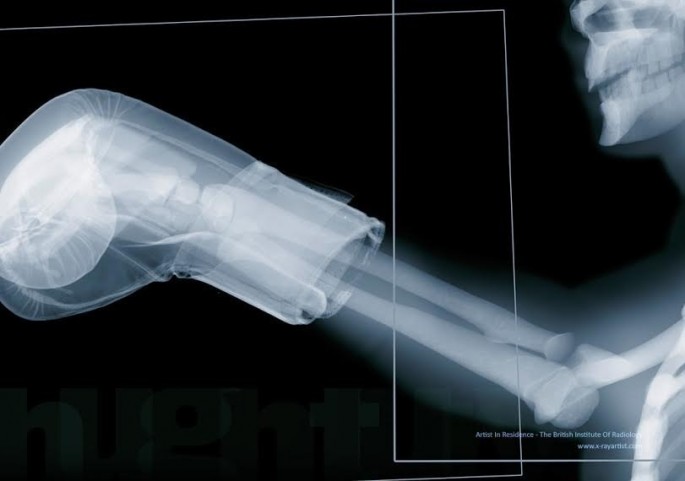

مجموعه ای بی نظیر تصاویر ایکس ری که شما را غافلگیر می کند.

به گزارش ایران خبر، معمولا از ایکس ری برای موارد پزشکی و علمی استفاده می شود و تصاویر خارق العاده ای تولید می کند .

در زیر تصاویری از بدن انسان در قالب ایکس ری را مشاهده می کنید.

در زیر تصاویری از بدن انسان در قالب ایکس ری را مشاهده می کنید.